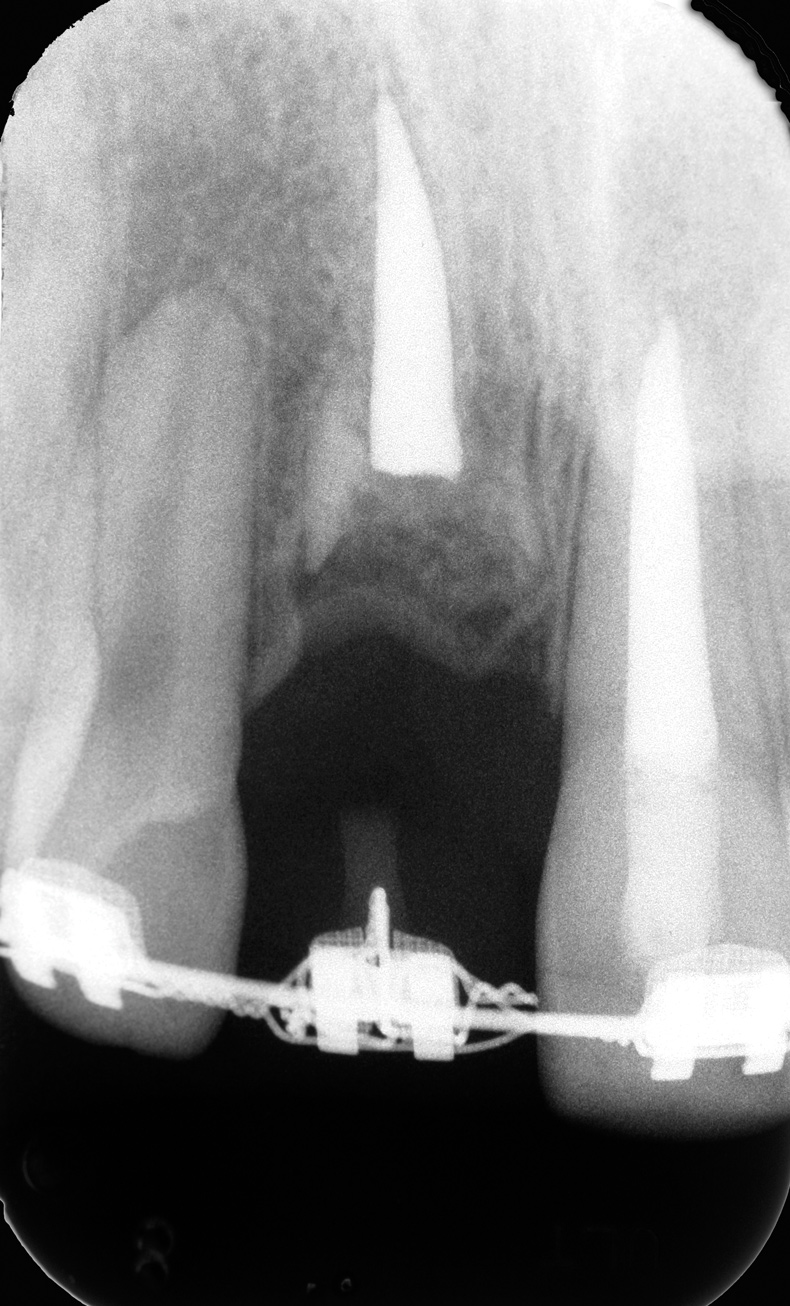

Fig 2. Age 8. Radiograph of teeth Nos. 8 and 9 at initial examination.

Figure 2

The patient's endodontic examination revealed a flexible splint from teeth Nos. 7 through 10 (Figure 1). Tooth No. 8 had a 3 mm x 3 mm class II fracture of the mesioincisal portion of the crown. Tooth No. 9 had a class IV fracture of the crown running labiopalatally from the remaining 2 mm of the crown to bone level on the palatal. A pulpotomy had been performed on the exposed pulp. Both teeth exhibited class III mobility. Teeth Nos. 7 through 10 did not respond to cold testing. None of the teeth were tender to palpation, and only tooth No. 9 had a slight positive response to percussion. Periodontal probings of tooth No. 8 were 4 mm to 5 mm on both the labial and palatal aspects. There was a narrow 12 mm probing on the straight palatal of No. 9; the remaining probing depths were 4 mm to 5 mm.2 A periapical radiograph showed both teeth Nos. 8 and 9 to have incompletely formed roots with wide-open foramina (Figure 2).